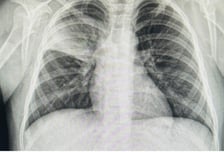

생명을 살리는 젊은 의사(醫師)가 뇌사상태에서 마지막까지 고귀한 생명 나눔을 실천하고 가톨릭 세례명인 '스텔라'(별)처럼 하늘의 별이 됐다. 서울성모병원은 가정의학과 전문의로 대학병원 임상조교수인 34세 여의사 이은애씨가 지난 6일 이 병원에서 이식 수술을 통해 심장, 폐장, 간장, 신장(2개)의 뇌사자 장기 기증으로 총 5명의 환자에게 새 생명을 선물했다고 7일 밝혔다. 고인은 중앙대 의과대학을 졸업하고 삼성서울병원에서 수련 후 순천향대부천병원 가정의학과에서 임상조교수로 재직하고 있었다. 지난 3일 오후 여의도 근처에서 친구들과 식사 중 머리가 아파 화장실에 갔고, 구토 후 어지러움을 느껴 화장실 밖 의자에 앉아 있던 중 지나가던 행인의 도움으로 근처 응급실로 이송됐다. 응급실 내원 후 경련이 일어났고 곧바로 의식이 저하돼 검사를 진행한 결과 뇌출혈(지주막하출혈)로 진단받았다. 이씨의 보호자는 수술해도 예후가 불량할 수 있다는 전문의 소견을 듣고 중환자실에서 보존적 치료를 받기로

마이코플라스마(마이코플라즈마) 폐렴이 중국을 휩쓸면서 인접국인 한국과 타이완·인도 등도 긴장하고 있다. 우리나라에선 마이코플라스마 폐렴이 대유행 수준은 아니지만 환자가 빠른 속도로 늘고 있다. 질병관리청에 따르면 최근 한 달새 감염환자는 126명(10월 4주차)에서 270명(11월 4주차)으로 2.14배 늘었다. 마이코플라스마 폐렴은 우리나라에서 3~4년마다 유행해왔다. 기존 유행 땐 1차 치료제인 마크로라이드 계열 항생제만 투여해도 대부분 증상이 완화됐다. 하지만 이번에 유행하는 마이코플라스마 폐렴은 이 약만으로 다스리기 힘들다고 한다. 어찌 된 영문일까. 6일 이대서울병원 소아청소년과 박영아(44·소아호흡기 전문의) 교수에게 그 이유를 물었다. ━Q. 기존의 항생제가 왜 듣지 않나. ━ "마이코플라스마 폐렴을 일으키는 폐렴균은 크게 두 종류로 나뉜다. 기존 1차 치료제인 마크로라이드계 항생제로 죽일 수 있는 균, 이 항생제에서도 살아남는 균이다. 이 가운데 후자가 마크로라이드계

'이 폐렴' 걸린 아이들 급증에도…질병청 데이터에 '아동병원' 빠진 이유

심하면 뇌염·뇌수막염을 불러오는 마이코플라스마 폐렴이 중국에 이어 한국 어린이 사이에서도 급증한 가운데, 질병관리청(이하 질병청)과 대한아동병원협회 간의 신경전이 치열하다. 마이코플라스마 폐렴 특성상 호발 연령대가 어린이이고, 어린이 환자를 가장 많이 진료하는 곳이 아동병원인데, 정부가 국내 마이코플라스마 폐렴 발병현황을 관리하기 위해 모집한 표본감시기관에 아동병원이 없어서다. 6일 머니투데이 취재에 따르면 질병청은 전국에서 '급성 호흡기 감염병' 환자가 얼마나 많이 발생하는지를 현황을 관리하기 위해 병원 218곳을 표본감시기관으로 선정했는데, 질병청은 이들 기관에서 주 단위로 감염자 현황 데이터를 취합해 '감염병 표본감시 주간 소식지'를 매주 발표한다. 지난달 30일 공개된 '2023년 47주차(11월 19~25일) 감염병 표본감시 주간소식지'엔 마이코플라스마 폐렴균, 인플루엔자 바이러스, 리노바이러스 등 바이러스별 감염 환자 비율을 포함해 노로바이러스 등 장관감염증, 수족구병 및